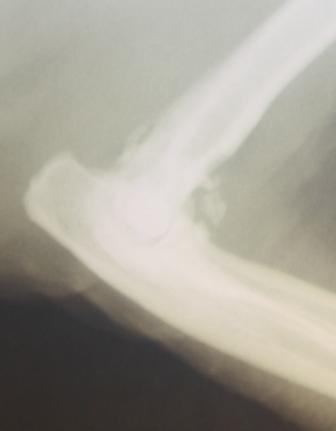

![]() |

| Her ser du tydelige påleiringer i albueleddet |

Gustav var i fin form og ble satt på medisiner tilpasset ham. I løpet av behandlingstiden har Gustav blitt så bra at vi har justert medisinnivået ned flere ganger, for å kunne holde ham på lavest mulig dose. Eierne er strålende fornøyd, Gustav er i kjemfin form og rører seg mye mer enn før.